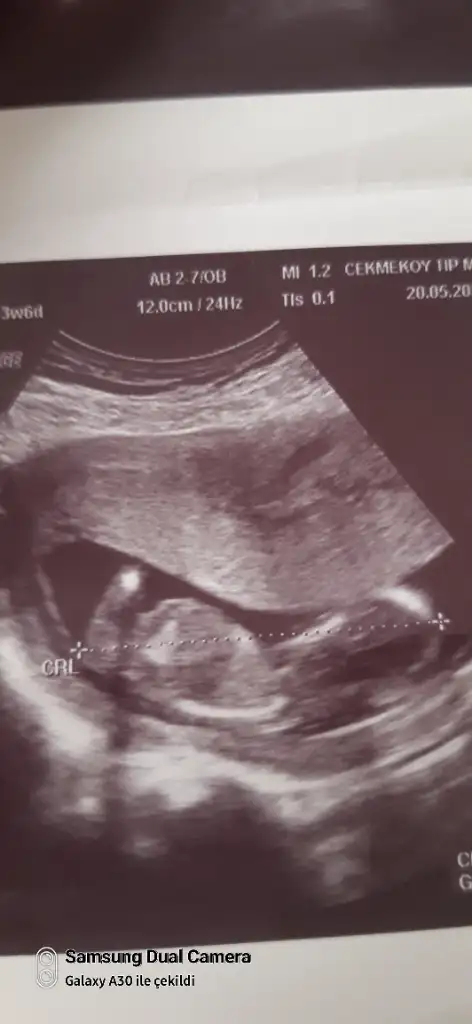

10+4 ten benim bebeğimin tahmini mümkün mü acaba bu görüntüden ☺️

Eklentiler

• 20250512_172908.webp

20250512_172908.webp

34,7 KB · Görüntüleme: 29

• 20250512_172903.webp

20250512_172903.webp

41,4 KB · Görüntüleme: 29